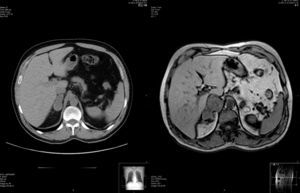

Varón de 48 años en el que, en TAC torácica realizada para estudio de enfisema pulmonar, se observa lesión nodular, inespecífica, en la glándula adrenal derecha, de 4×2,5×2cm. Para completar estudio de masa adrenal incidental, se realiza RM, en donde se evidencia masa adrenal derecha, heterogénea, de 6,8×4,4×3,9cm, en íntimo contacto con el pilar del diafragma y la vena cava inferior, a la cual comprime, compatible con carcinoma o lesión metastásica (fig. 1). En el momento de la realización de la resonancia el paciente denota la aparición de un dolor constante de intensidad leve en hipocondrio derecho.

De crecimiento rápido, como se puede apreciar en este caso (fig. 1), por debajo de 5cm suelen ser asintomáticos; son sus síntomas más frecuentes el dolor abdominal y lumbar, y la sensación de efecto masa en hipocondrio, así como la astenia y el adelgazamiento10. Por encima de 8cm, casi todos los casos comunicados presentaban metástasis a distancia en el momento del diagnóstico1,3,10.

En los análisis de laboratorio y hormonales, no se suelen detectar alteraciones significativas, y en las pruebas de imagen no se ha descrito ninguna característica específica de este tumor, si bien los tumores derechos con frecuencia se extienden por la vena cava inferior hasta el pilar diafragmático derecho1,7,8. En nuestro caso el tumor se extendía hasta la cápsula hepática.